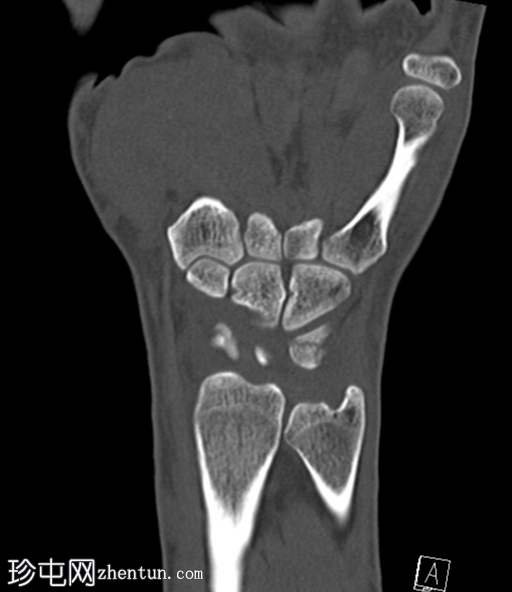

冠状位片

平扫

CT轴位、矢状位和冠状位片显示三角骨背侧粉碎性撕脱性骨折。

未见其他骨折。